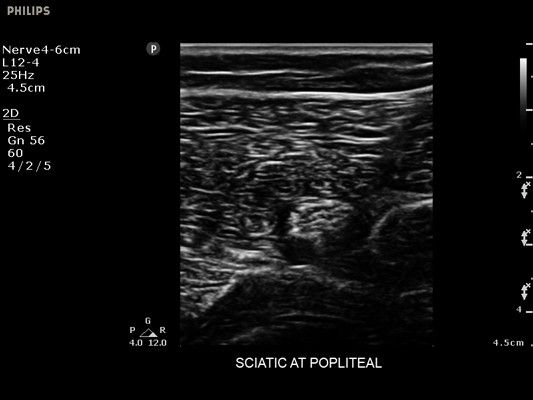

• Усиленная визуализация иглы без потери качества изображения окружающих тканей

• Метки центральной линии на датчиках L12-4 и C6-2 для упрощения внеплоскостной навигации

• Диагностика нервов

• Линейный УЗИ датчик Philips L12-4